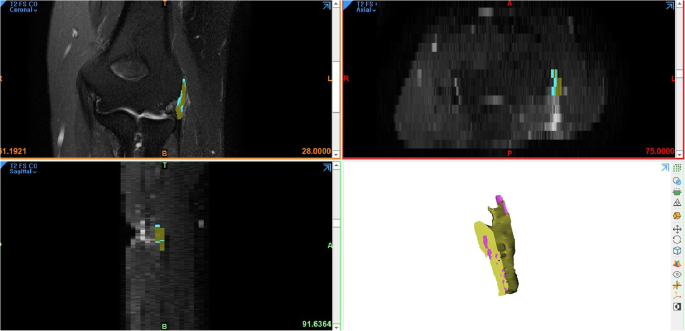

The digitized MR imaging data in the Digital Imaging and Communications in Medicine (DICOM) format files were imported into 3D reconstruction modeling software (Mimics® 22.0, Materialise, Antwerp, Belgium) (Fig. 1). Fat-suppressed T2-weighted FSE sequence images were adopted for 3D reconstruction because those sequences are considered suitable for the evaluation of tendon pathology such as tendinosis and tendon tear [12]. The boundary of the common extensor tendon of each participant on the fat-suppressed T2-weighted FSE sequence was determined by agreement of the four specialists. The proximal boundary of the common extensor tendon was set as the insertion site of the common extensor tendon located in the lateral humeral epicondyle, and the distal end was set as the articular surface level of the radial head (Fig. 2). The common extensor tendon lesion boundary was defined as the area of high signal intensity, which showed a different signal intensity from the normal tendon within the boundary of the common extensor tendon. Mimics® software was used to convert voxels within the common extensor tendon boundary to density masks (Fig. 3). The voxels corresponding to the common extensor tendon lesions and normal common extensor tendon within the common extensor tendon boundary were separately converted to density masks. Density masks based on voxels within the common extensor tendon boundary were defined as region of interests (ROIs) of common extensor tendon, and density masks based on voxels of common extensor tendon lesions were defined as ROI of common extensor tendon lesion. Mimics® software was also used to automatically calculate the volume of ROI of common extensor tendon and the volume of ROI of common extensor tendon lesion (Fig. 4). The proportion occupied by the volume of ROI of common extensor tendon lesion in the volume of ROI of common extensor tendon was defined as the proportion of lesion volume of common extensor tendon (pLCET). pLCET values were calculated for each participant and used for analysis.

A screenshot of the three-dimensional (3D) graphic processing software. Digitized magnetic resonance imaging data in DICOM format were imported and the coronal, sagittal, and axial views of the computed tomography data were obtained in 3D graphic processing software (Mimics® 22.0, Materialise, Antwerp, Belgium)

Three-dimensional (3D) reconstructed region of interests (ROIs) of the common extensor tendon and the lesion of the common extensor tendon. a 3D reconstructed ROI of the common extensor tendon. b 3D reconstructed ROI of the lesion of common extensor tendon. (C) 3D reconstructed ROIs of the common extensor tendon and the lesion of common extensor tendon